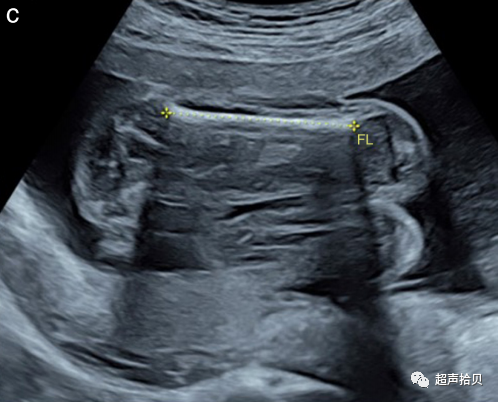

1. 测量应按照严格的质量标准和按照ISUOG实践指南以标准化的方式进行;

2. 应该获得一个图像来记录每个测量值。图1显示了适合于胎儿生物测量的静止图像示例;

图1标准胎儿生物测定法。超声测量:(a)头围(HC)、(b)腹围(AC)和(c)股骨长度(FL)。

股骨长度(FL)

解剖:

1. 测量FL 时应清楚显示股骨两端的骨化中心。测量骨化骨干的最长经线。

2. 与参考标准对应的方法一样,测量时股骨和声束之间的角度,在 45° 和 90° 之间。

3. 现代超声机器的技术改进已经减小了波束宽度,这影响了横向方向的胎儿测量。这具有临床意义,应使用最近的测量图表,因为使用较旧的测量图表可能会导致对 FL 的高估。

游标放置:

1. 每个游标都放置在骨化骨干的末端,如果可见,则不包括股骨远端骨骺(图1c)。测量应避免包括三角形刺状伪象。